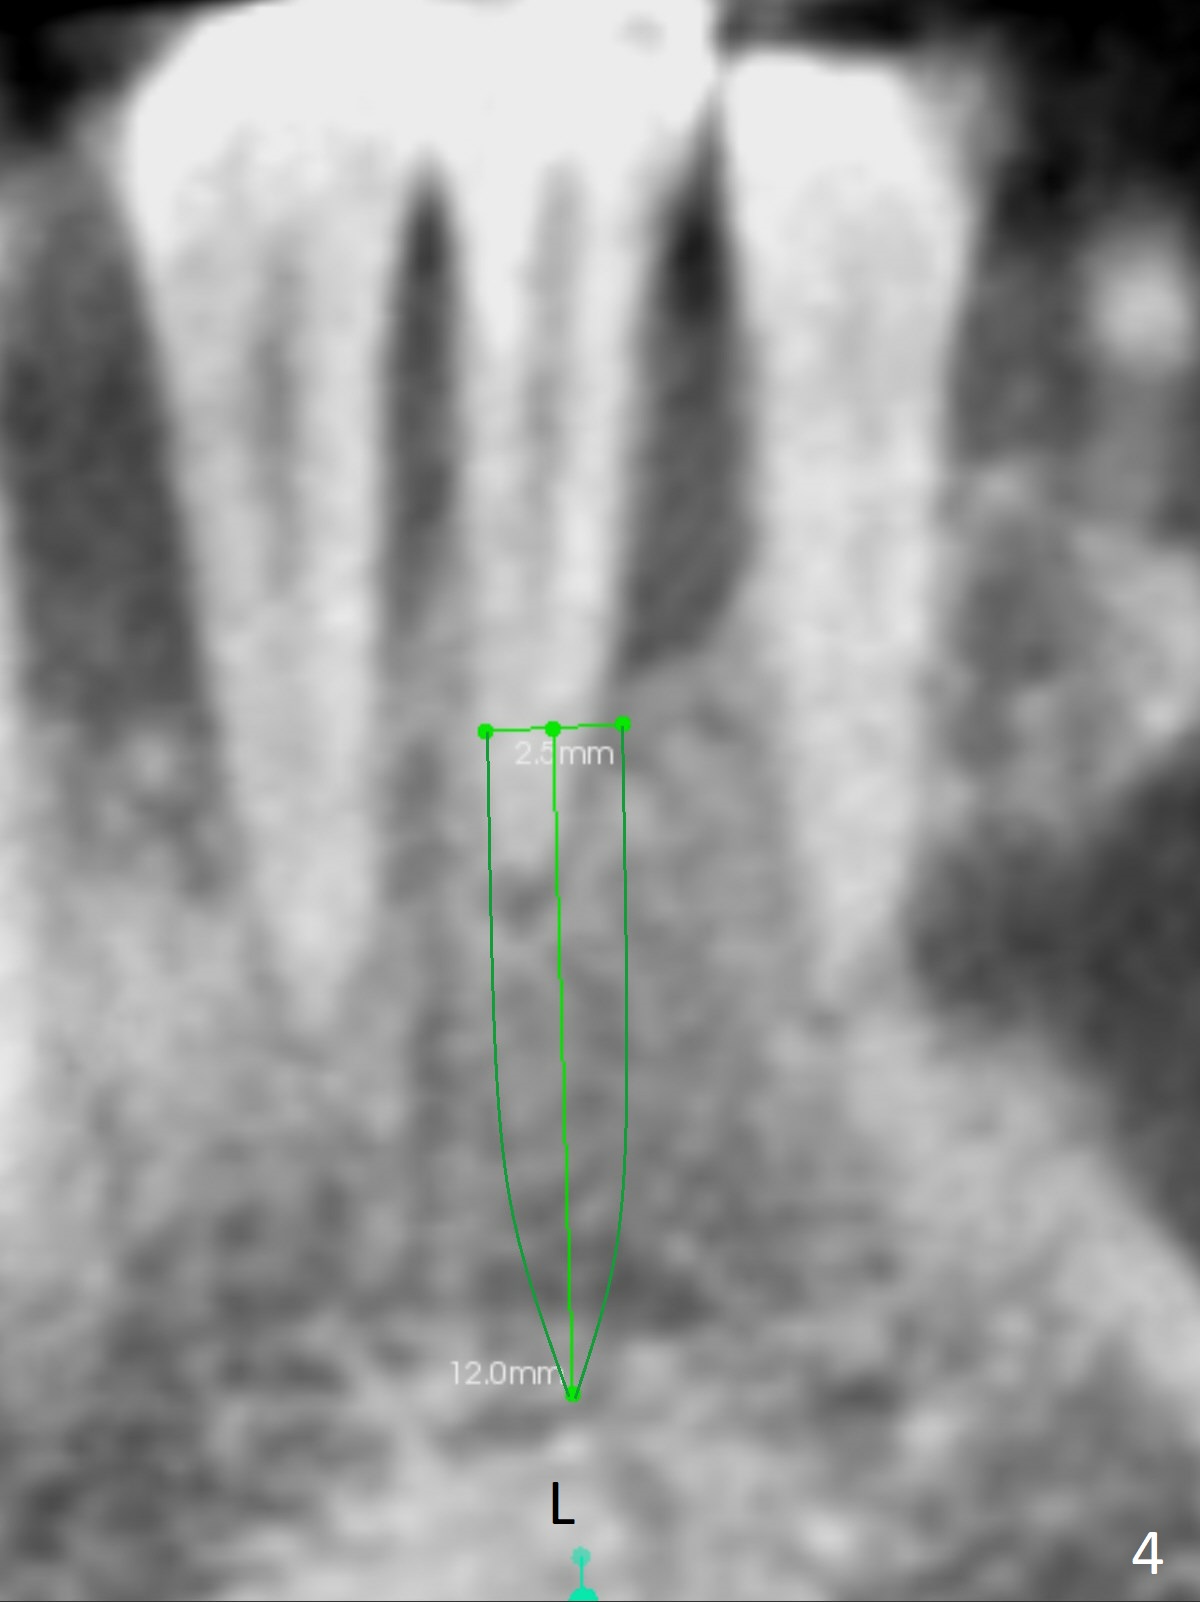

A 44-year-old woman has had bone loss at the tooth #25 for the last 4 years (Fig.1 *). Since the bone is narrow buccolingually (Fig.2 (CT coronal section)), a 1-piece implant with 2.5 mm in diameter is proper (Fig.3); but 12 mm in length makes the implant close to the lingual plate (Fig.2-4 L), with possible perforation. To avoid the latter, a shorter implant seems more appropriate for the site (Fig.5). Osteotomy is initiated in the apex with two fingers holding the buccolingual plates. Take PA preop. There is no buccal or lingual plate when the tooth is extracted; the socket bottom is flat buccolingually (Fig.6).